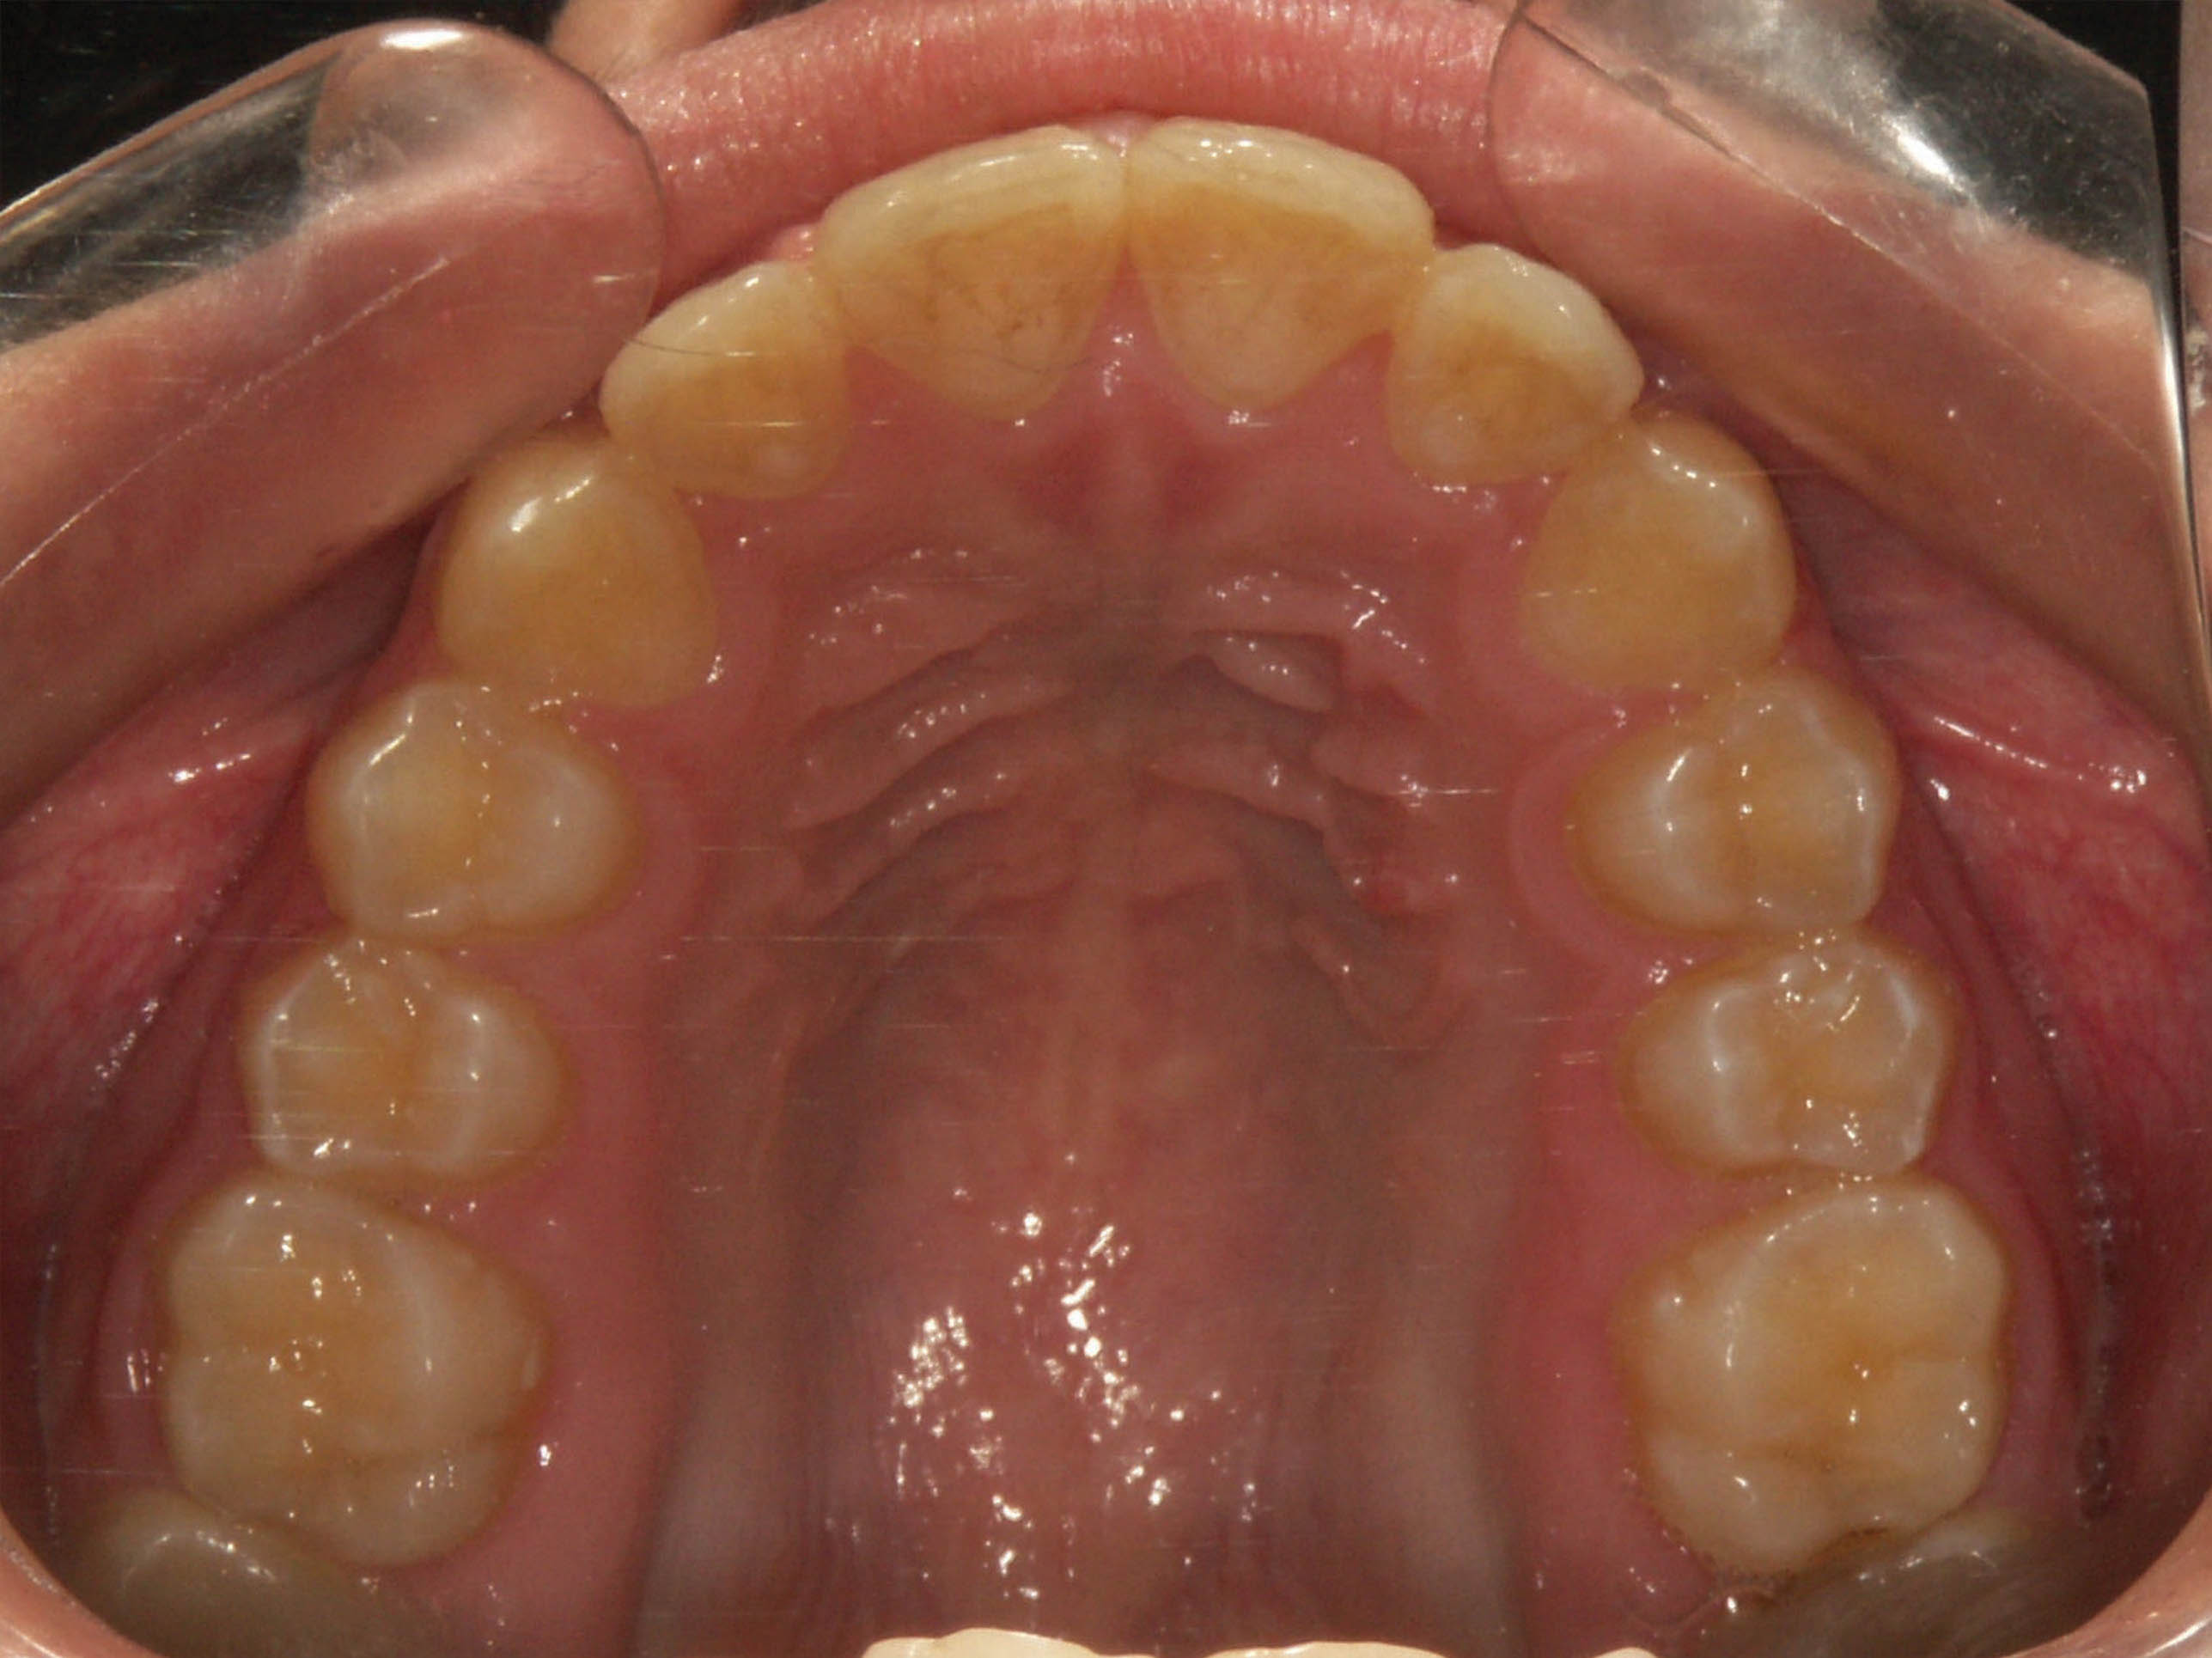

بعد از درمان